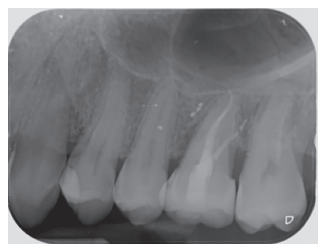

Caso clínico: se presenta el caso de un varón de 28 años, que acudió a consulta por la presencia de unos restos radiculares en localización de primer molar superior izquierdo. Se realizó un autotrasplante dental, siendo el diente donante el tercer molar superior izquierdo, que se trasplantó al alveolo del primer molar, mostrando buena evolución clínica y radiográfi ca.

Clinical case: a clinical case of a 28-yearold man is presented, who went to dental clinic for removal of left fi rst molar roots. An autotransplant was performed using left third molar as donor tooth, which was transplanted into fi rst molar alveolus, showing promising clinical and radiographic evolution.

Por tanto, debido a las altas tasas de éxito descritas en la literatura, el objetivo del presente caso clínico es evaluar clínica y radiográficamente la realización de un autotrasplante con el ápice cerrado, para reponer un primer molar superior izquierdo, como alternativa terapéutica a la colocación de un implante en un paciente adulto.